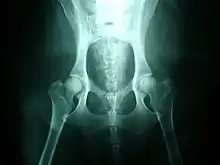

Hip dysplasia is diagnosed with radiographs of the pelvis. There are several standardized systems for categorising dysplasia, set out by reputable bodies. The most widely used systems include the following:

Radiographs can be sent to OFA for grading and certification.[11] This system rates a dog's hip joint on a seven-point scoring system. The test relies on interpretation of a radiograph of the dog's hips, which are then assigned a score by three independent radiologists: Excellent, Good, Fair, Borderline, Mild, Moderate and Severe.[12]